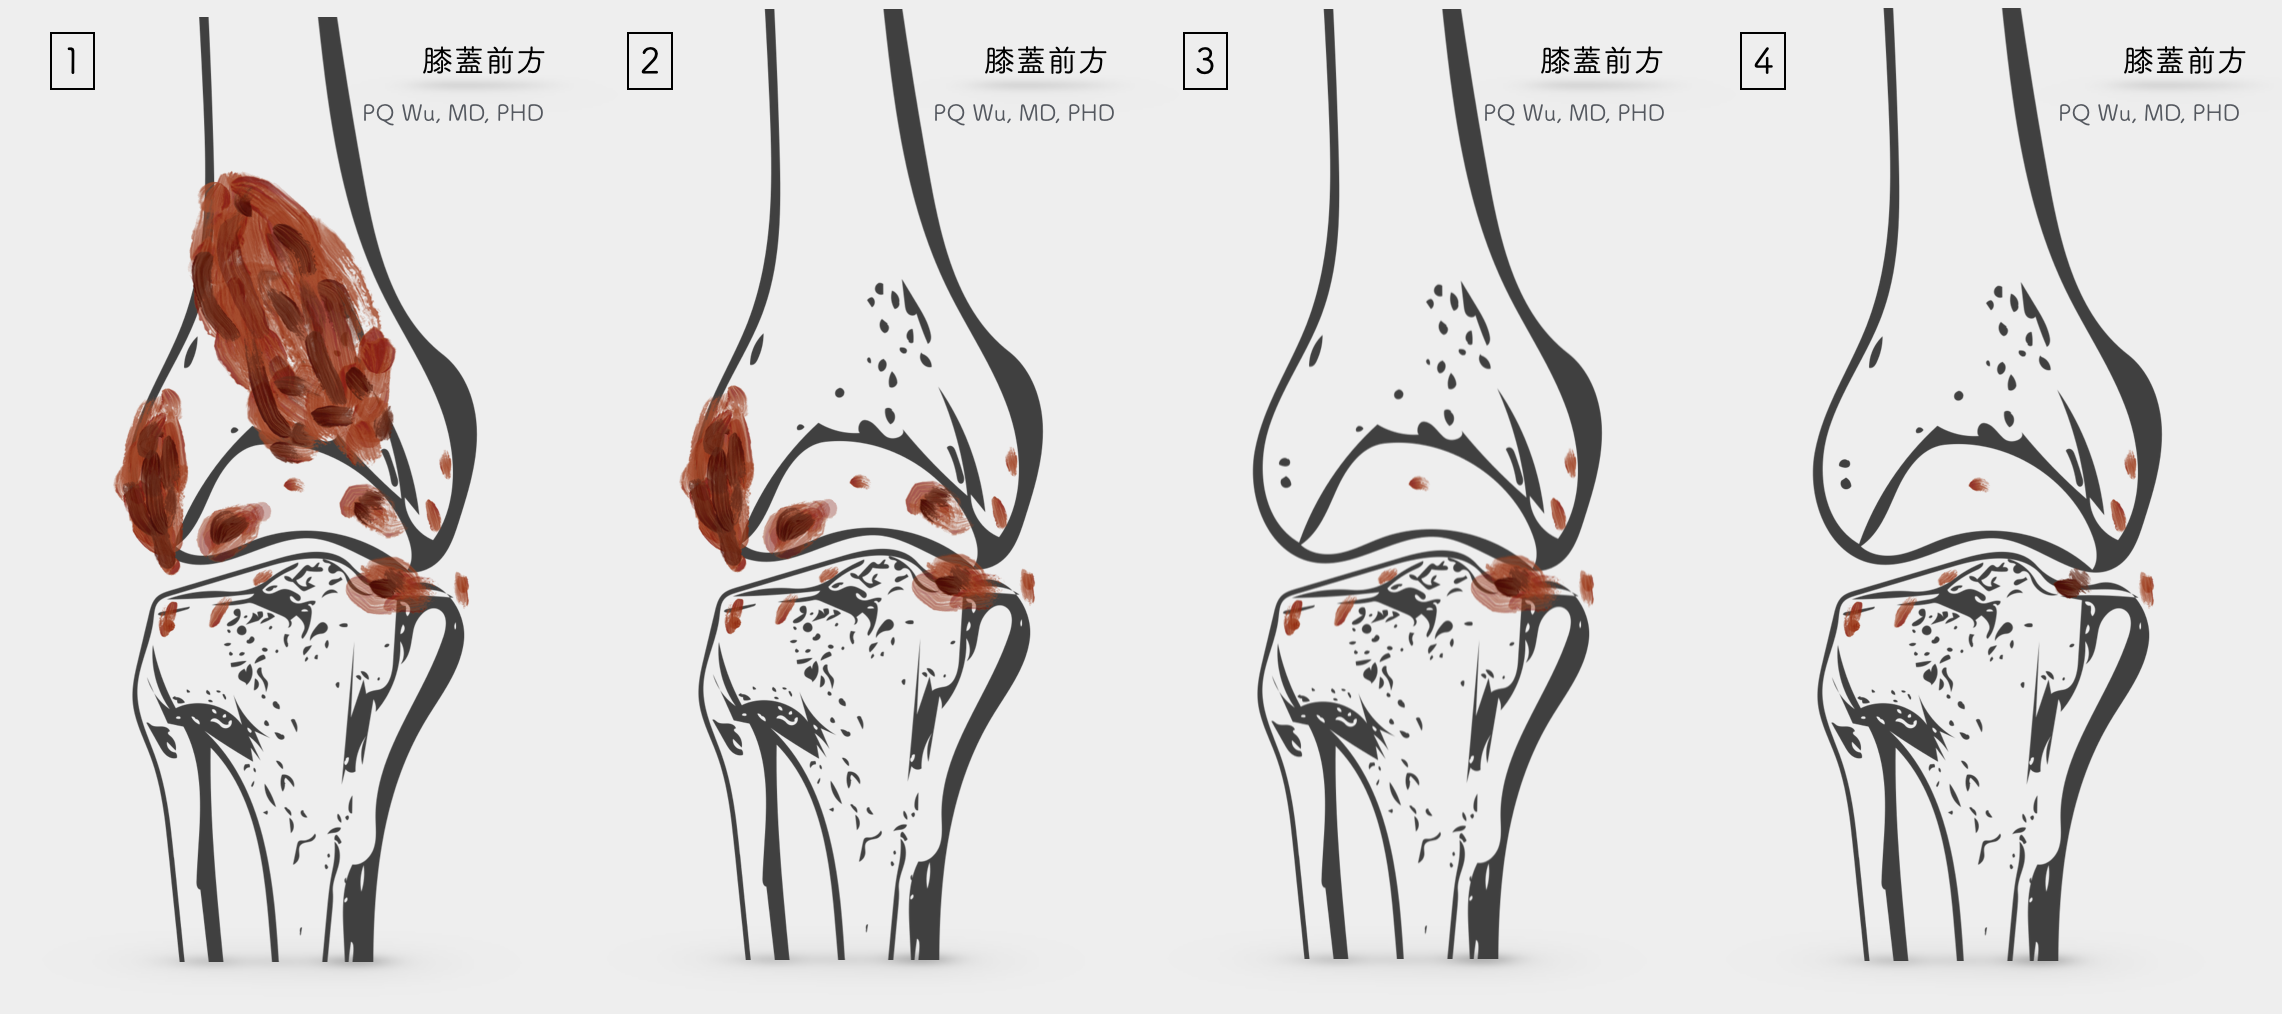

因此,對於這樣的疾病,國際上大多採用複合的方式來作為治療。在過去的方法,醫師先進行第一次手術,將膝蓋前方的腫瘤清除。之後使用石膏固定兩週後,再行第二次手術將膝蓋後方的腫瘤清除。接著在手術六週後,加以局部的低劑量放射線治療,以減少腫瘤復發的機會。

而我們台北榮總骨骼肌肉腫瘤治療暨研究中心將這個傳統的方式進行修正,將第一、第二次手術合併在一起,手術後不用石膏固定,反而在手術後隔天開始積極的復健運動。根據我們的研究結果,這個方法可以使病患得到更好的手術後功能恢復。我們團隊的這個成果,在2012年發表於知名的骨科醫學期刊 Clinical Orthopaedics and Related Research(CORR)中(*),目前已經成為全球治療彌漫型的腱鞘巨細胞瘤的標準做法。

(5) 膝蓋後方之腫瘤,常與神經血管發生沾黏 (5) 再將關節腔外的腫瘤,儘可能的切除 (7) 打開後側關節腔,移除關節內的腫瘤 (8) 可能殘餘部分之腫瘤於關節腔中與神經血管壁上